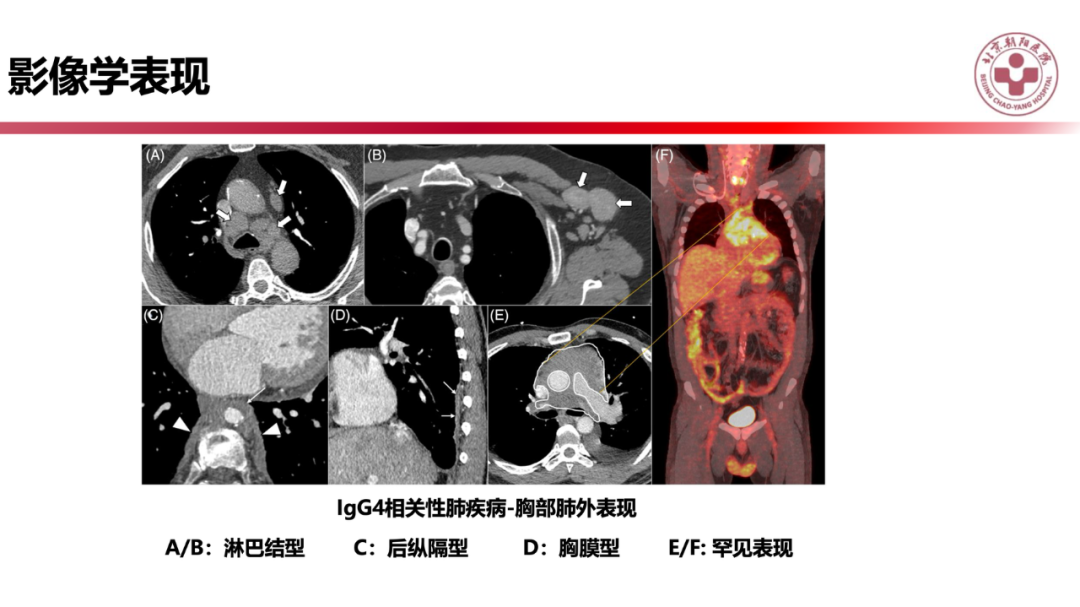

IgG4相关性肺疾病的诊断思路是什么?

来源:北京朝阳医院放射介入影像中心